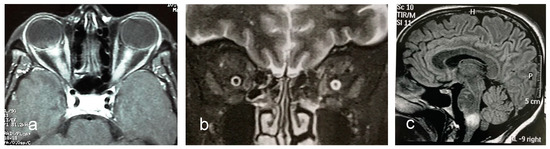

3.6. MRI Features